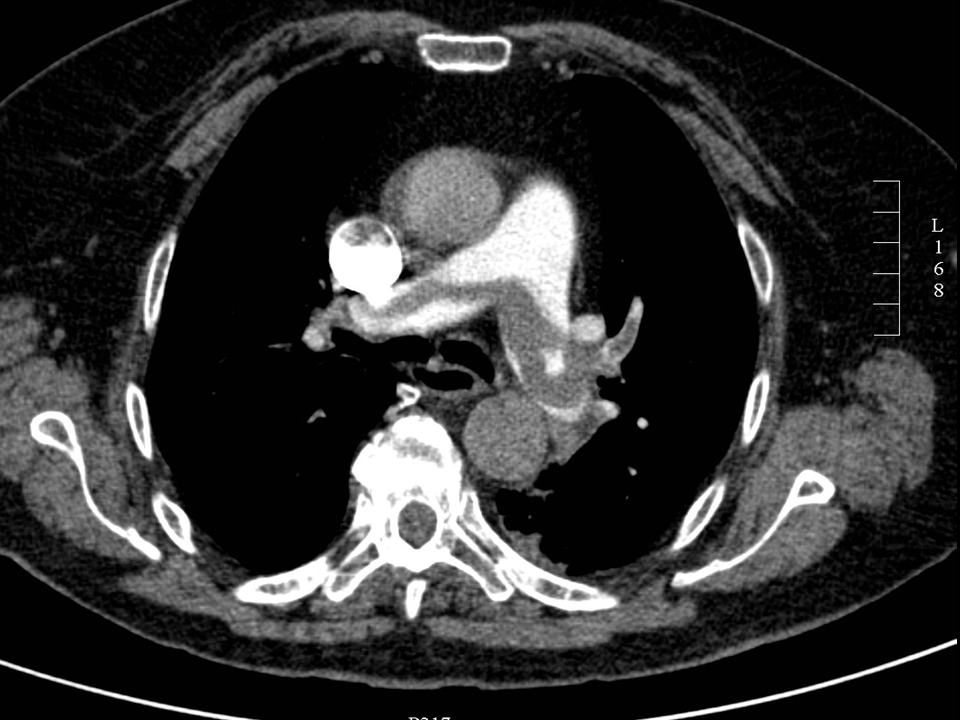

• Aortic rupture occurs after rapid deceleration it is usually located at the transition of the aortic arch and the descending aorta, as the aortic arch more mobile than the descending aorta, it can be diagnosed with CT angiography.

• Aorta aneurysm rupture – aorta dissection

If the patient is stable, immediate CT angiography is the diagnostic choice. In case of suspected dissection CTA should be performed with ECG gating.